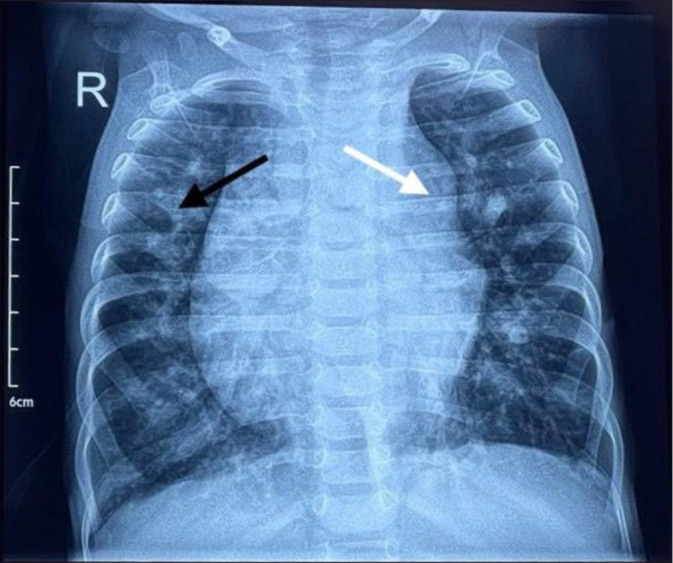

摘要左心室憩室(LVD)是一种罕见的先天性异常,其特征是左心室壁异常突出。它通常在儿童时期被发现,因为它通常与胸腹中线缺陷和其他先天性心脏异常有关。在这里,我们报告了一个10个月大的男婴,他患有下腹部血管病和脐膨出,需要手术治疗,术后断奶困难。我们讨论了独特的挑战,需要细致的规划和执行,以优化右心室功能和预防肺动脉高压在这类患者。

Left ventricular diverticulum (LVD) is a rare congenital anomaly characterized by an abnormal outpouching of the left ventricular wall. It is often identified during childhood, as it is commonly associated with midline thoracoabdominal defects and other congenital heart abnormalities. Here, we present a 10-month-old boy with a LVD and omphalocele posted for surgical management who had difficulty weaning in the post-operative period. We discuss the unique challenges that necessitate meticulous planning and execution to optimize right ventricular function and prevent pulmonary arterial hypertension in such patients.